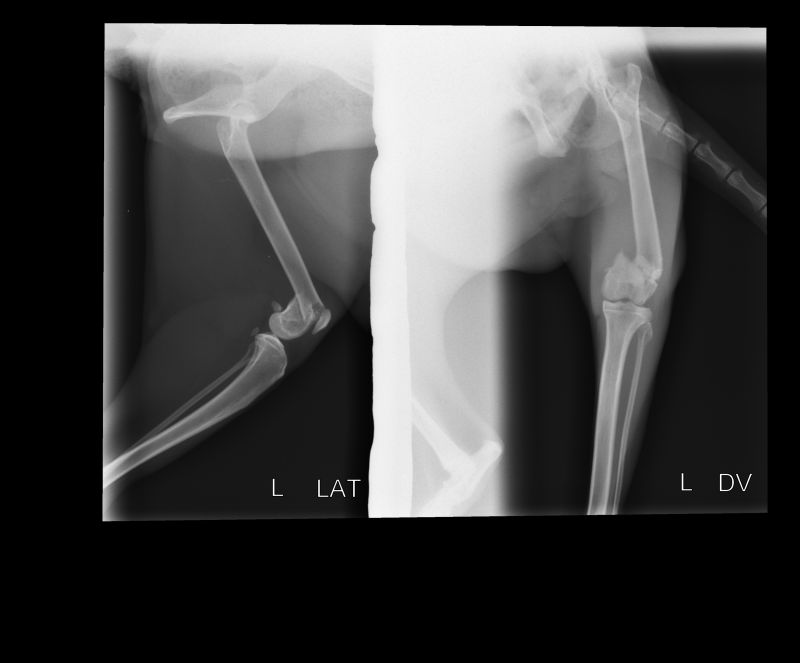

Abnormal Pathology on your pet

Shown on x-ray images which we have taken over the years.

Some interesting patient cases